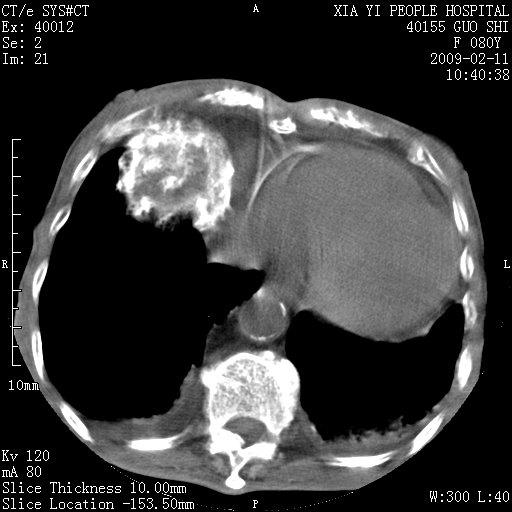

以下是引用随光逐影在2009-2-16 16:34:00的发言:[br]1)考虑右前纵隔皮样囊肿。2)双侧少量胸腔积液。

以下是引用zjzjr在2009-2-16 17:30:00的发言:[br]支持囊性畸胎瘤 双侧少量胸腔积液。